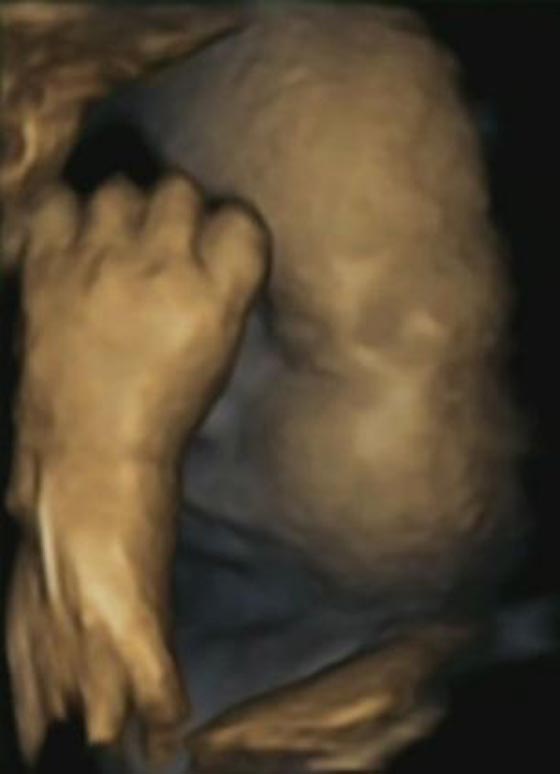

يقول الاطباء ان صورة جديدة تم التقاطها في رحم الام قد تكون اوضح دليل على ان الأطفال الذين لم يولدوا بعد يشعرون بالإجهاد الذي يصيب الأم ويتأثروا به. ويظهر الجنين في الصورة الرائعة وقد وضع يده تحت ذقنه مما يشير الى انه هو ايضا يعاني من التوتر والضغط.

ويقول باحثون في جامعة لانكستر وجامعة دورهام أنهم لاحظوا انه حينما تكون الام مجهدة او تحت ظروف ضغط  فأن جنينها يعاني من القلق ايضا، ومن ثم يحاول تهدئة نفسه بلمس وجهه تماما كما نفعل نحن الكبار، ونحن نفعل ذلك من خلال امساك رأسنا بكلتا يدينا. اما الجنين فيلمس وجهه باستعمال يد واحدة فقط وهذا يهدئ من روعه.